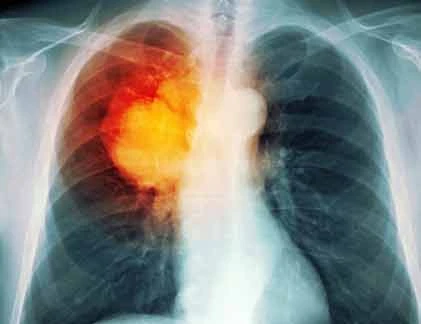

• Ho không dứt

• Đau ngực, đặc biệt là khi hơi thở sâu

• Thở khò khè hoặc khó thở

• Ho ra đờm có máu

• Mệt mỏi